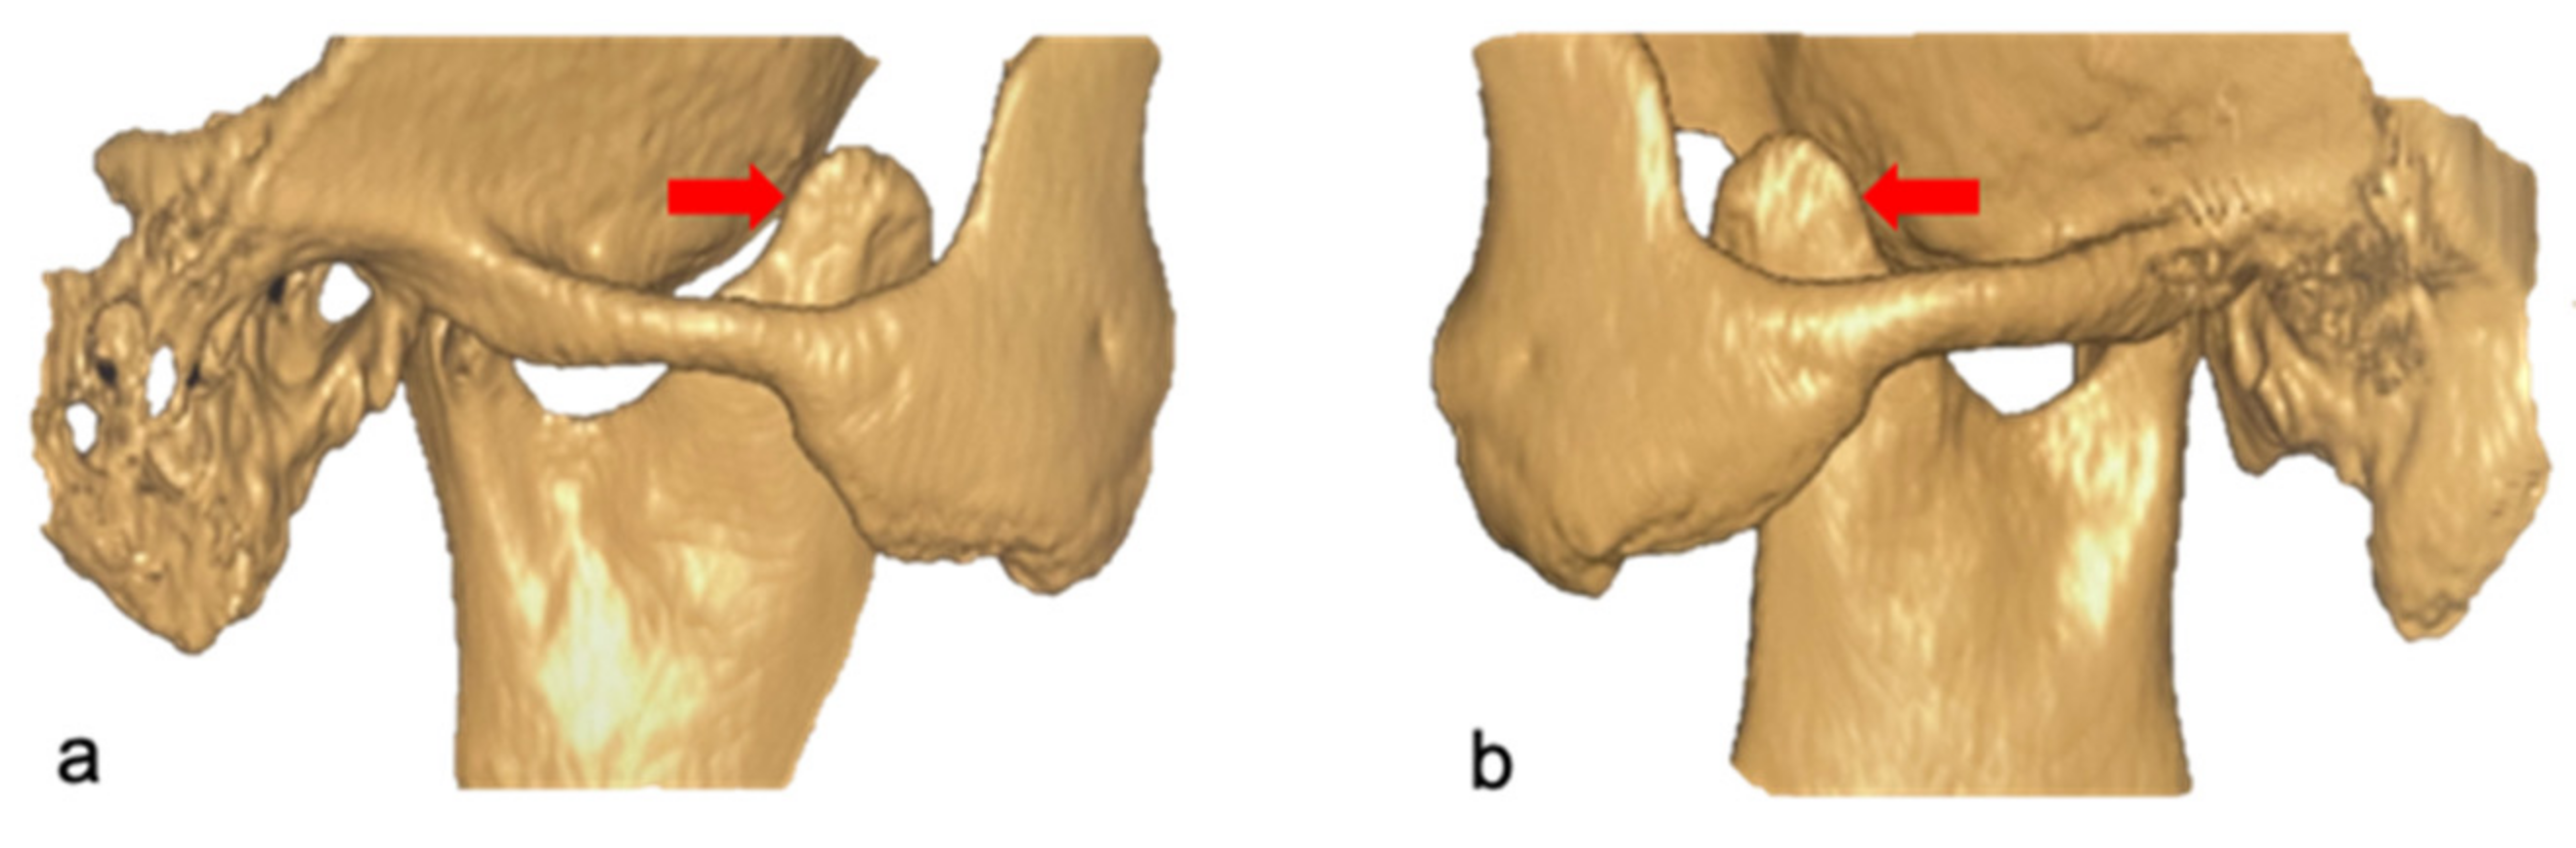

- Wang, W.; Xu, B.; Zhang, B.; Lou, H. Temporomandibular joint ankylosis contributing to coronoid process hyperplasia. Int. J. Oral Maxillofac. Surg. 2016, 45, 1229–1233. [Google Scholar] [CrossRef]